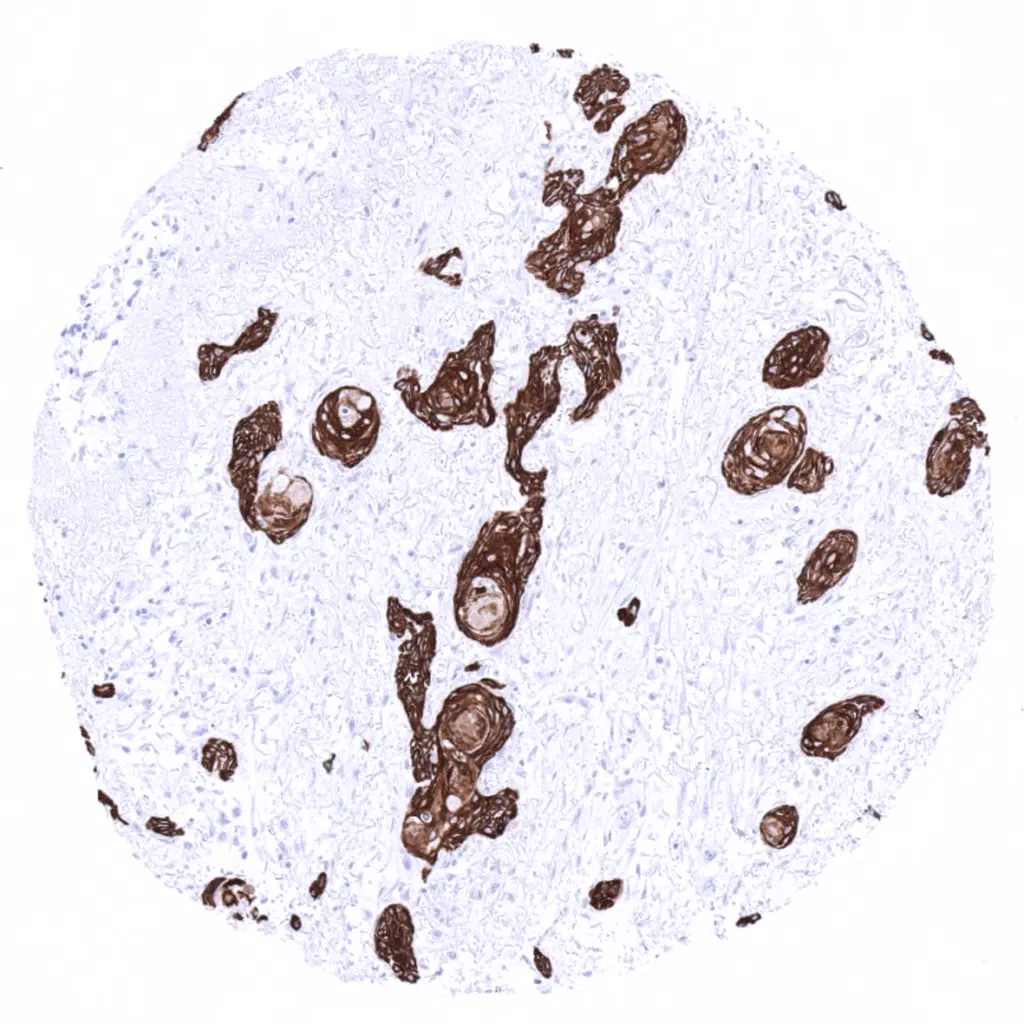

Vulvar squamous cell carcinoma with strong cytokeratin 19 positivity.